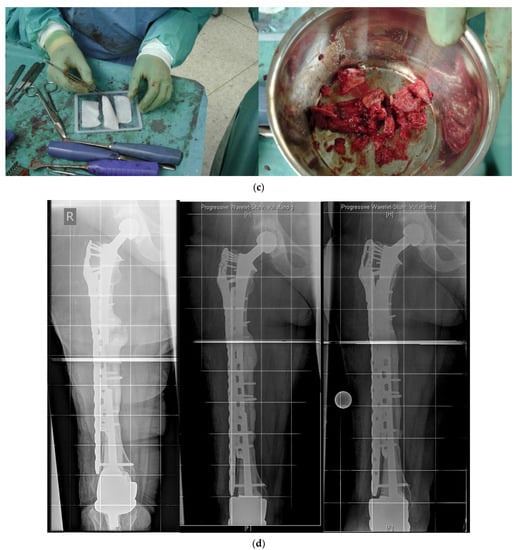

Hence, a special concept improving the bicortical screw fixation around intramedullary devices called the LOQTEQ® VA Periprosthetic Plate or ‘periprosthetic hinge plate’ was established by the company, aap Implantate AG. Multiple insertable hinges create the possibility to place the screws bicortically and alongside the enclosed stem. The square of the two polyaxial locking screws of the hinge constitutes 15 degrees to each direction. Since a central screw can be attached separately, further angle stabilization of the hinges can be achieved. The hinge is not attached to a plate hole, which could be staffed additionally with monocortical screws or cable cerclages in the diaphysis (Figure 3).

Figure 3.

(a) LOQTEQ VA Periprosthetic Plate (with kind permission of aap Implantate AG, Berlin, Germany). (b) Insertable hinge with each of the two variable angle screw options (with kind permission of aap Implantate AG, Berlin, Germany). (c) Periprosthetic fracture around a cemented stable total hip revision arthroplasty. (d) LOQTEQ VA Periprosthetic Plate with mounted aiming device. (e) LOQTEQ VA Periprosthetic Plate with four inserted hinges. (f) Variable angle screw placement around the hip revision stem. (g) Postoperative X-rays. Four hinges with each of the two variable angle screw options were used to fix the plate around the hip stem.

A biomechanical study investigated the characteristics of the LOQTEQ® VA Periprosthetic Plate in comparison with the standard locking compression plate with locking attachment plate, for the treatment of periprosthetic fractures in a Vancouver B1 fracture model.

The LOQTEQ® VA Periprosthetic Plate showed superior biomechanical results (axial stiffness and cycles to failure) compared to the standard locking compression plate in combination with the locking attachment plate [21].